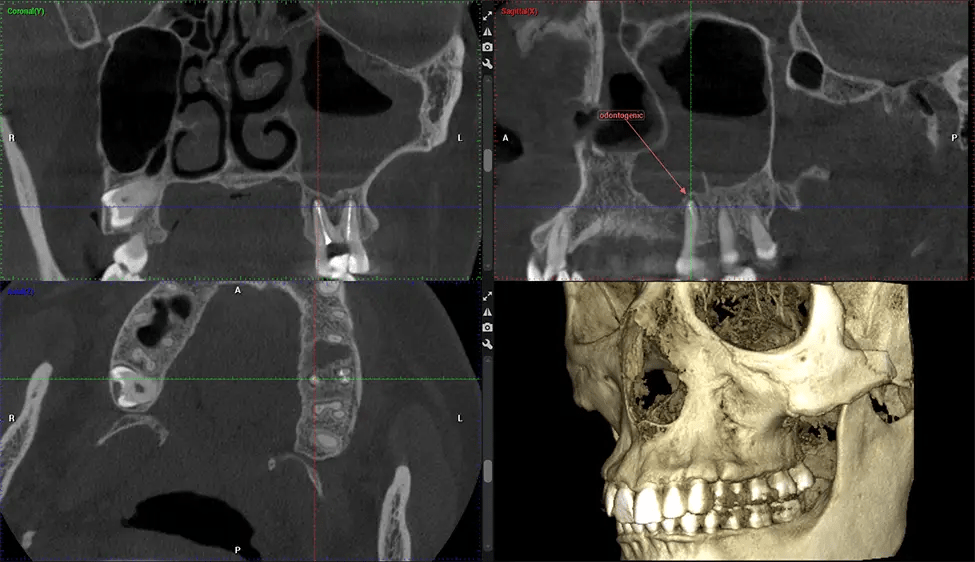

Oral and Maxillofacial Surgeon Complex oral surgeries, orthognathic (jaw) surgery, and removal of impacted teeth. Offers precise, three-dimensional visualization of the skull, jaw, and craniocervical junction to enhance diagnostic accuracy and minimize surgical risks.

Orthodontist Assessing facial asymmetry, planning orthognathic surgery, and managing cleft lip and palate and sleep apnea. Provides a comprehensive view of the craniofacial complex to better plan treatments and evaluate outcomes.

Upper Cervical Chiropractor Diagnosing structural problems in the C1-C2 vertebrae, assessing misalignment and instability, and evaluating chronic pain. Enables precise, weight-bearing views of the upper cervical spine, helping to identify abnormalities that inform targeted, non-invasive therapies.

ENT Physician Diagnosing obstructive sleep apnea (OSA) and evaluating sinus and nasal cavity anatomy. Visualizes the entire pharyngeal airway to measure volume, pinpoint constrictions, and plan corrective surgery if needed.